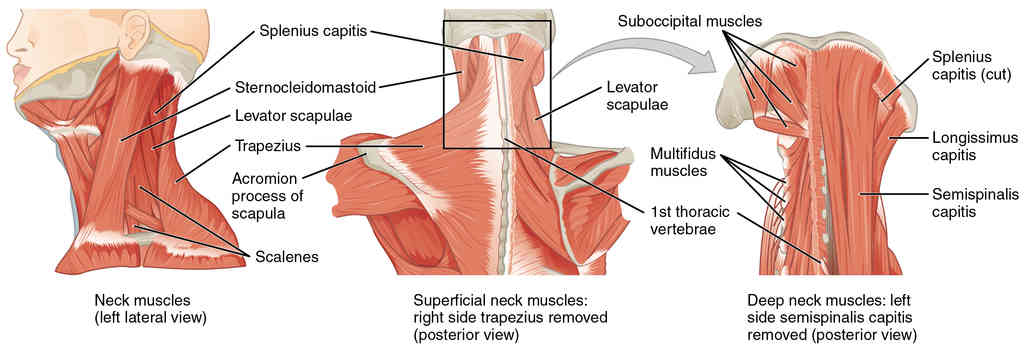

This page is under construction. For now, it is just a resource of the images found in the OpenStax Anatomy and Physiology Handbook. It wil slowly change into a revision tool. Each slide has a number. Use this to refer to the slide. When completed, it will have an unlabelled section, with labelled slides in parallel. On the unlabelled slides, write your answer and use the labelled slide to assess yourself. Keep track by also noting the number on each slide. Improvement at each attempt is important, more so than full marks on a first attempt.